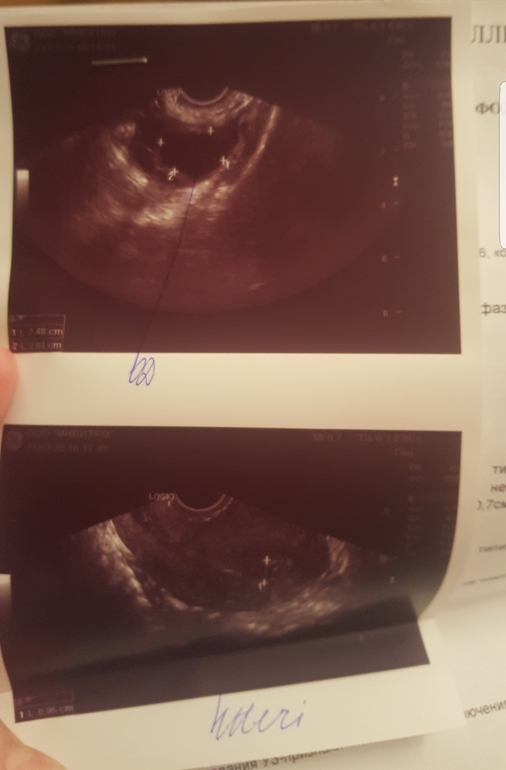

Девочки, добрый вечер. Сегодня на 14 день цикла была на узи. Врач толком не сказала ничего. Говорит фолликул 24 мм в правом яичнике.

Но на 10 дц этот фолликул был 20мм , после этого был укол зря 10000 ед.

Вопрос: кто разбирается в фото узи, на что это похоже? Фолликул, желтое тело или киста? Жидкости нет. Я врачу не доверяю, она явно была ни в чем не уверенна, да еще и достала свои тетради с записями подеркнутыми салатовым маркером. Как в институте.. И выставила меня из кабинета, чтобы я ждала заключения. Вот собственно оно.

На верхнем фото совулировавший фоллик. Они выглядят как амёбы, жт я пока не вижу. Видимо, вот-вот произошла овуля. Странно, что жидкости не увидели. Вот так выглядит фоллик до овуляции